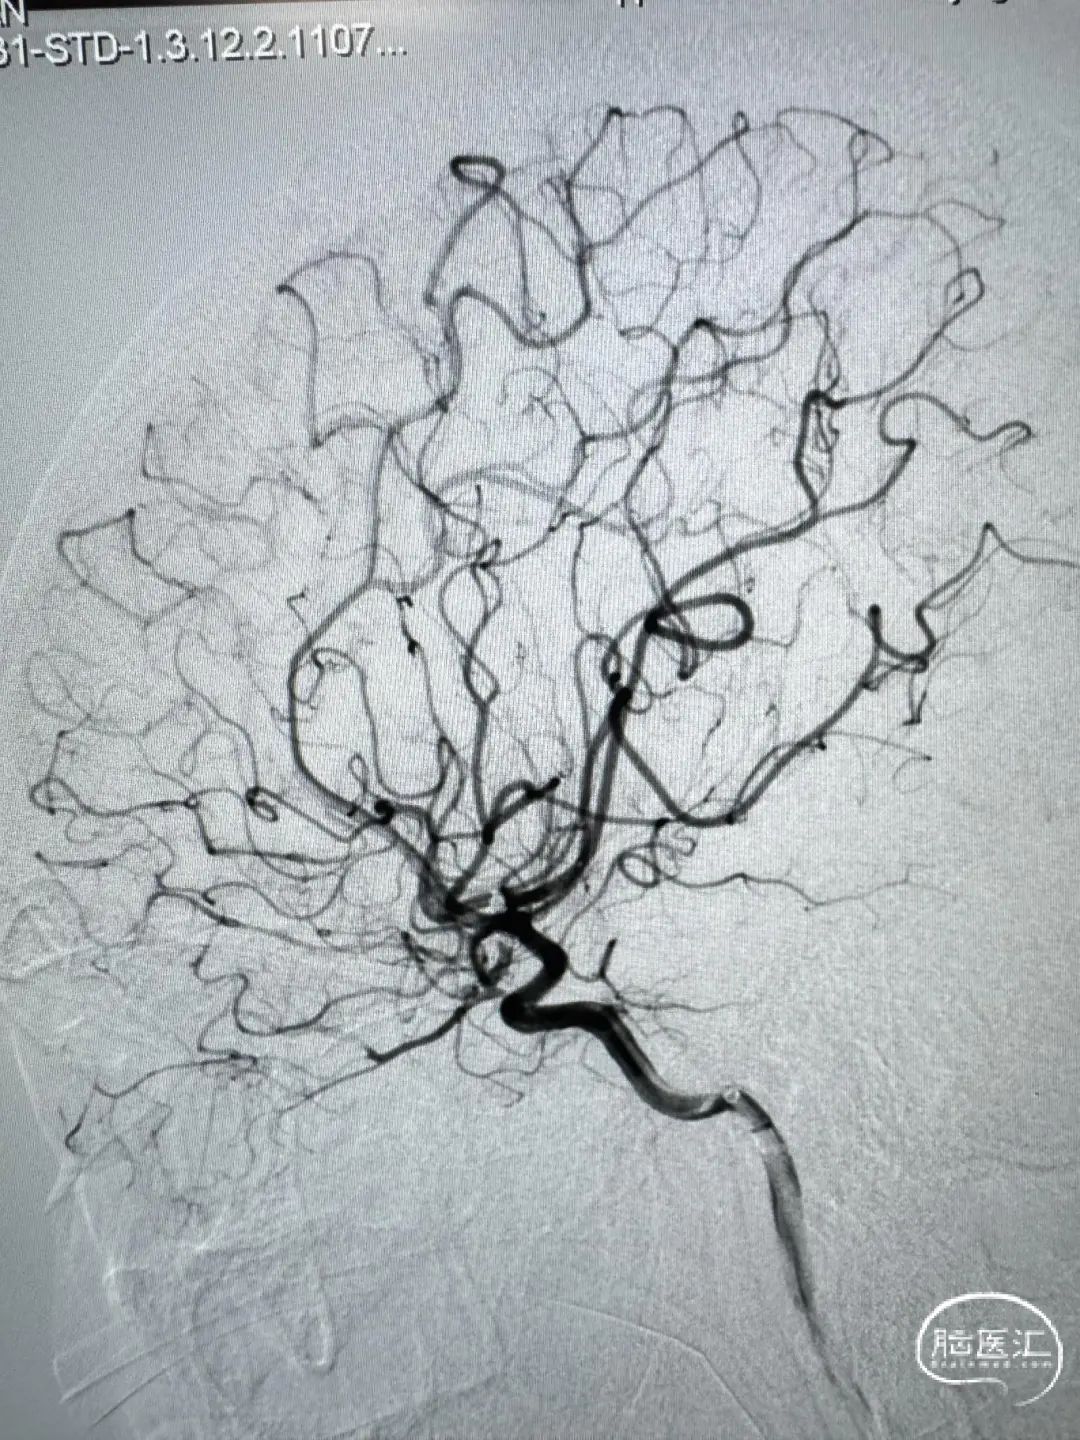

术后正侧位造影。

动脉瘤完美栓塞,一个支架,两根微导管,一根微导丝主导全程,填塞致密。

该例病案,“花开一支,各表一朵”,远端分叉处动脉瘤为责任动脉瘤,但颞干处动脉瘤呈“分叶状”。本次手术最大的难点在于颞干处动脉瘤的处理策略,分期处理的话,在血管痉挛期风险极大提高。如同期处理,从M1水平放支架,对瘤颈没有意义,且两个支架在M1中段可能会有交汇,对豆纹动脉的影响太大。如放在颞干,后期远端动脉瘤万一复发,那补救手术的难度太高。另颞干处为小型动脉瘤,分叶状,如超选两根微导管分区填塞,则空间不够。以上多方面考虑,本例动脉瘤对术者手感考虑比较大,最后颞干处动脉瘤弹簧圈裸栓成功,且经济成本明显下降。

另有报道,动脉瘤尾端在M1段打开可能会波及豆纹动脉,故尽量选用水平段释放支架,对穿支血管尽量减少影响。